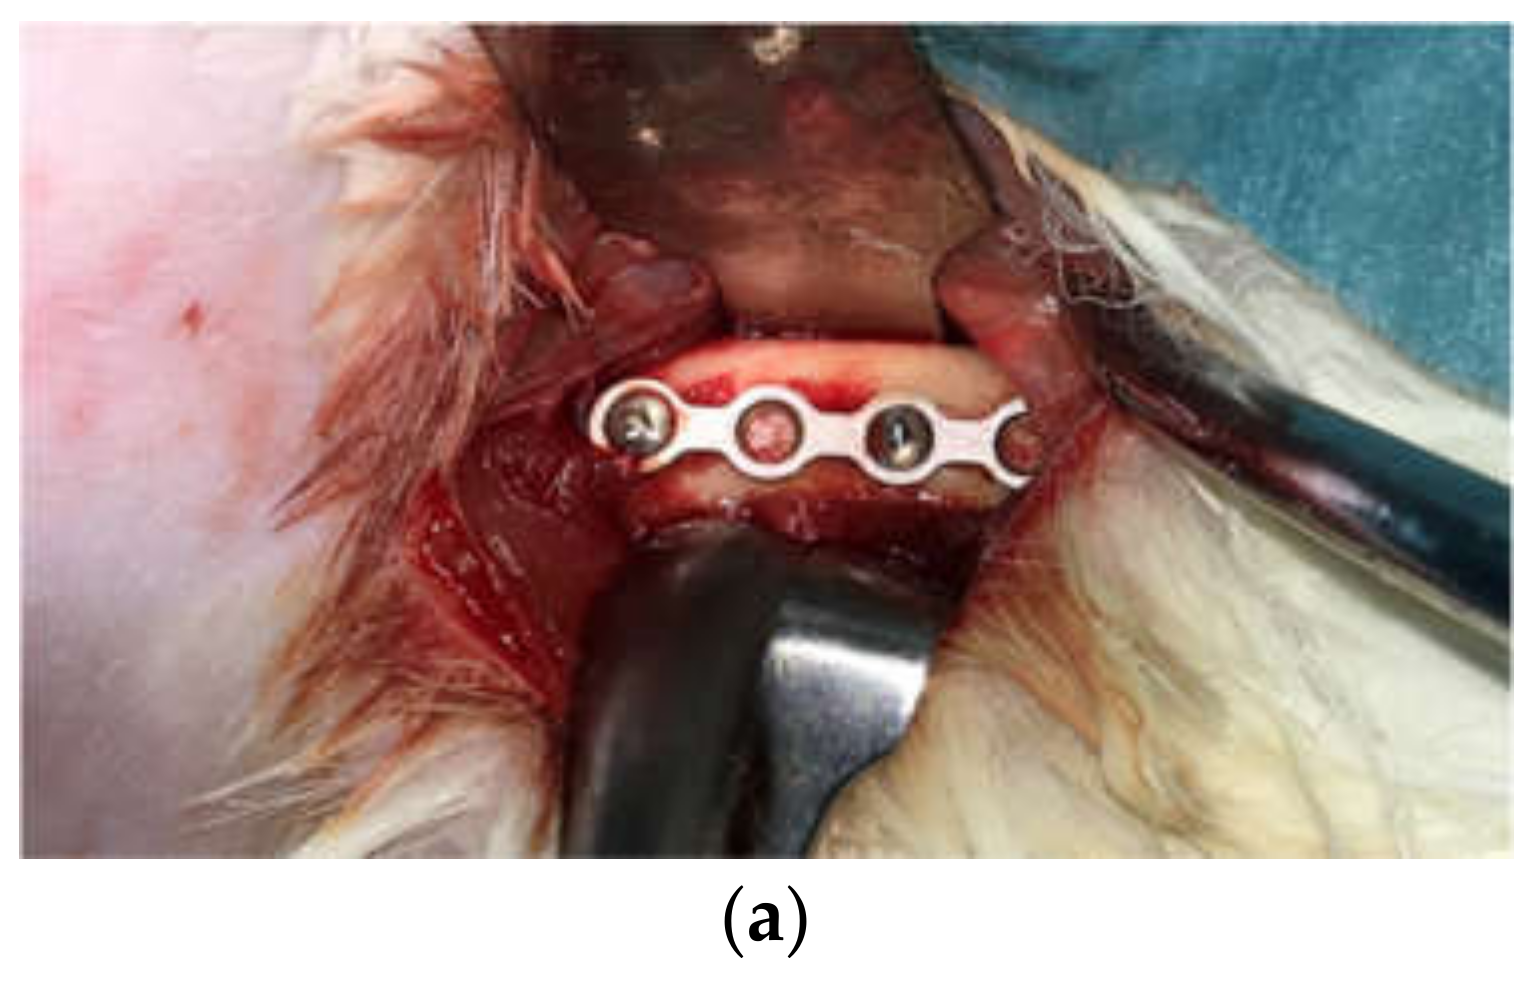

4.2.2. Implantation of Titanium Plates and Screws